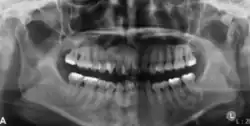

In its early stages, central ossifying fibroma (COF) appears as a small, well-defined radiolucent lesion due to its fibrous tissue content. Differential diagnoses at this stage include periapical pathology, central giant cell granuloma, and ameloblastoma.[22][23] As the lesion matures, it exhibits a mixed radiolucent-radiopaque appearance due to progressive calcification.[22] At this stage, it should be differentiated from other mixed jaw lesions such as fibrous dysplasia, calcifying epithelial odontogenic tumour, adenomatoid odontogenic tumour, and condensing osteitis.[22] In its mature form, COF may appear predominantly radiopaque, resembling lesions like odontomas, osteoblastomas, or osteosarcomas radiographically.

COF typically presents with well-defined, smooth, and often corticated borders. As a central lesion, it originates within the medullary bone and expands concentrically in all directions.[24] With growth, it may cause tooth displacement, root resorption, inferior displacement of the mandibular canal, and loss or alteration of the lamina dura of adjacent teeth.[25]

In conclusion, COF most commonly occurs in the mandible and expands from a central epicenter. Radiographically, it presents as a well-defined mixed-density lesion,[26] and Cone Beam CT (CBCT) plays a crucial role in its accurate diagnosis and assessment.

Central Ossifying Fibroma (COF) typically presents as a painless swelling in the posterior mandible, though maxillary involvement can also occur.[31] Larger lesions may lead to facial asymmetry and displacement of adjacent teeth.[32] Radiographically, COF appears as a well-circumscribed, mixed radiolucent–radiopaque lesion with a characteristic sclerotic border, and the degree of radiopacity reflects the stage of mineralization.[33] Cone-beam computed tomography (CBCT) offers detailed evaluation of cortical expansion, root displacement, and internal architecture.[34]